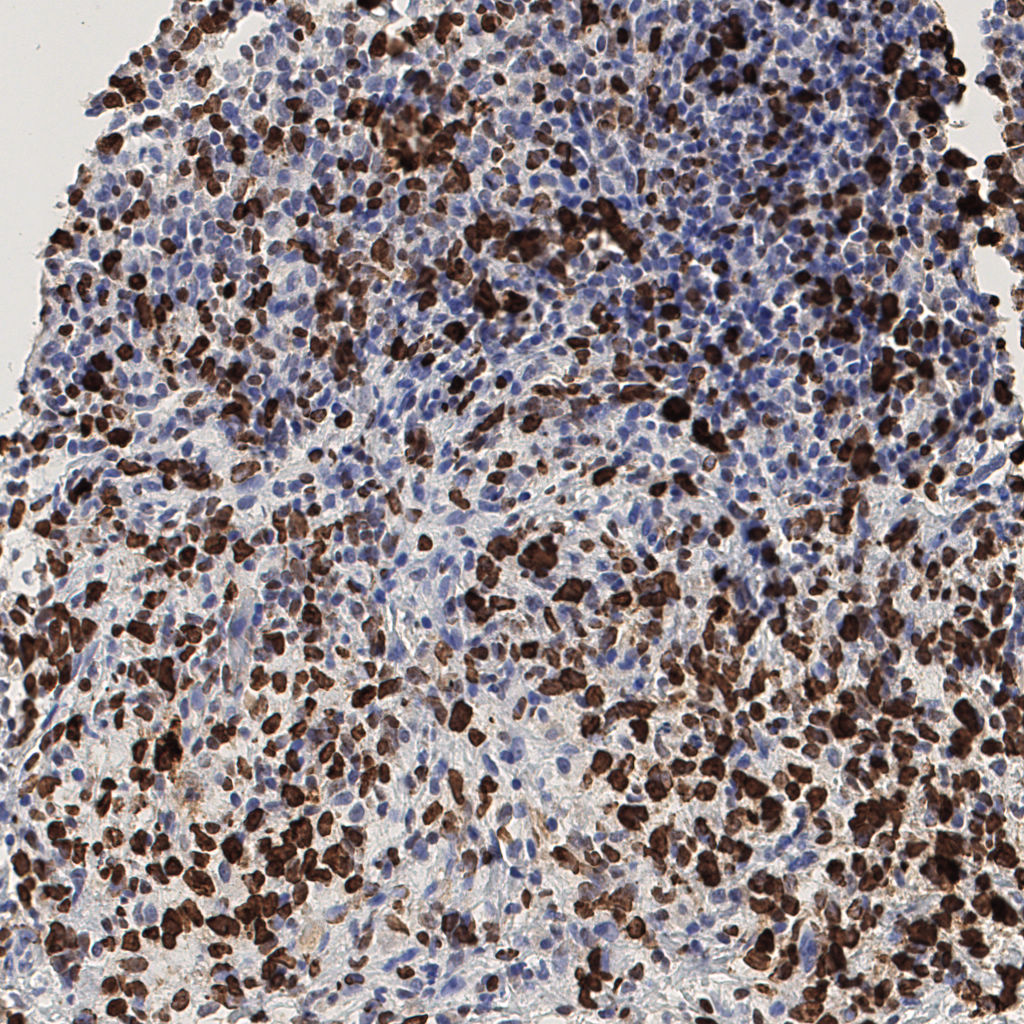

7.85%

Ki67 指数

阴 1104

阳 94

切片统计

总切片

1953

有效

288

已标记

有效率

15%

标记后

标记前